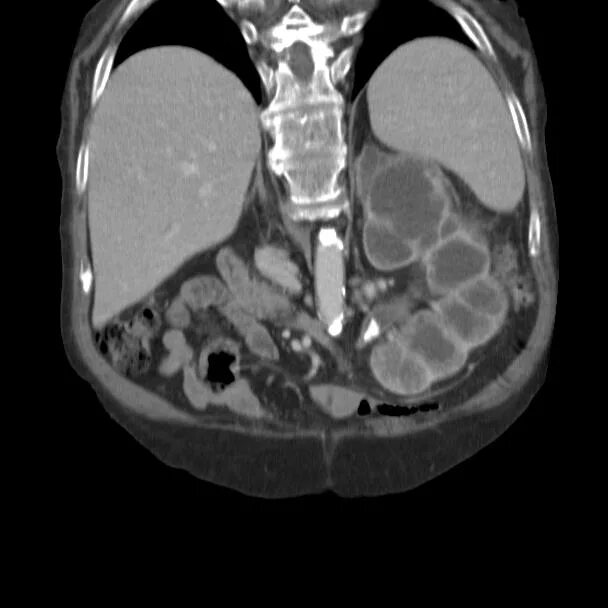

Пиелонефрит кт